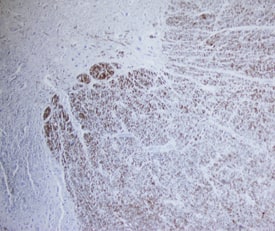

FABP8/M‑FABP in Human Spinal Cord.

FABP8/M-FABP was detected in immersion fixed paraffin-embedded sections of human spinal cord using using Mouse Anti-Human FABP8/ M-FABP Mono-clonal Antibody (Catalog # MAB5866) at 15 µg/mL overnight at 4 °C. Before incubation with the primary antibody, tissue was subjected to heat-induced epitope retrieval using Antigen Retrieval Reagent-Basic (Catalog # CTS013). Tissue was stained using the Anti-Mouse HRP-DAB Cell & Tissue Staining Kit (brown; Catalog # CTS002) and counter-stained with hematoxylin (blue). Specific staining was localized to white matter. View our protocol for Chromogenic IHC Staining of Paraffin-embedded Tissue Sections.